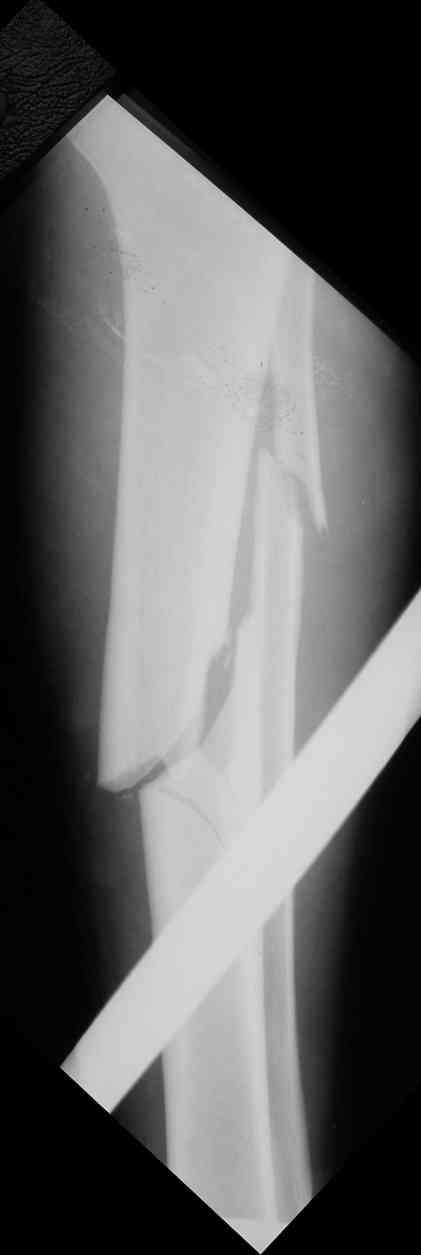

Дорогой Александр. Имею скромный опыт использования системы Fixion при переломах плеча, бедра и тибии. Всего 18 наблюдений с сентября 2006 г. Результаты отличные. Гвоздь индивидуален для каждого медуллярного канала. Легко имплантируется как в узкий, так и в деформированный канал. Это позволяет применять метод интрамедулярного остеосинтеза без ненужных потерь времени операции, флюороскопии и реально снижает крвопотерю и операционный риск. Удаление происходит без проблем. Особенно интересны больные с ипсилатеральными переломами бедра и голени.

Да, спасибо за интересные иллюстрации. Получилось очень симпатично. На большеберцовой кости непременно надо было винты? Там же был торцовый упор, перелом в средней трети?